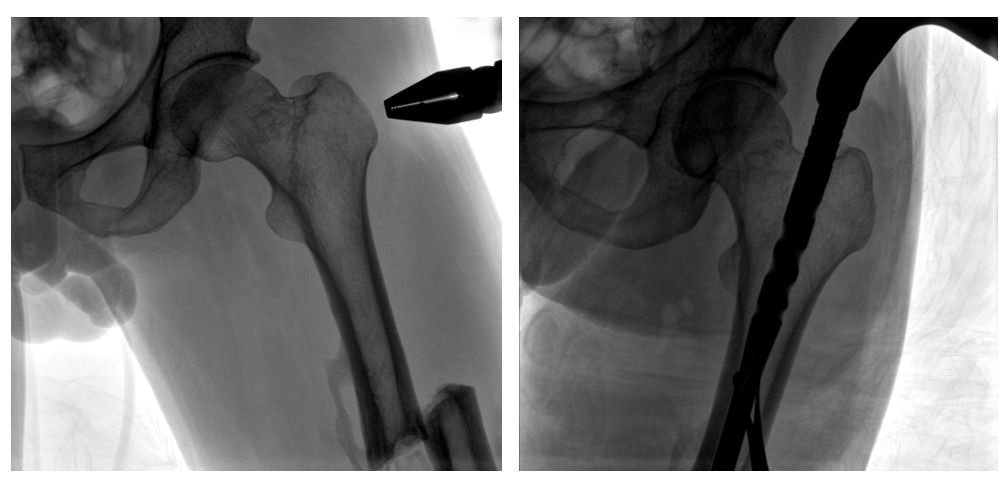

普爱医疗PLX119C大平板一体式C形臂采用30CM×30CM的平板探测器,在脊柱和长骨骨折等骨科手术治疗中,获取更大视野、更清晰的骨折部位图像,能够有助于医生在术中及时了解和评估骨折部位的对位、对线情况,且能进行长度和角度测量,为进一步提高手术质量提供强有力的支持。